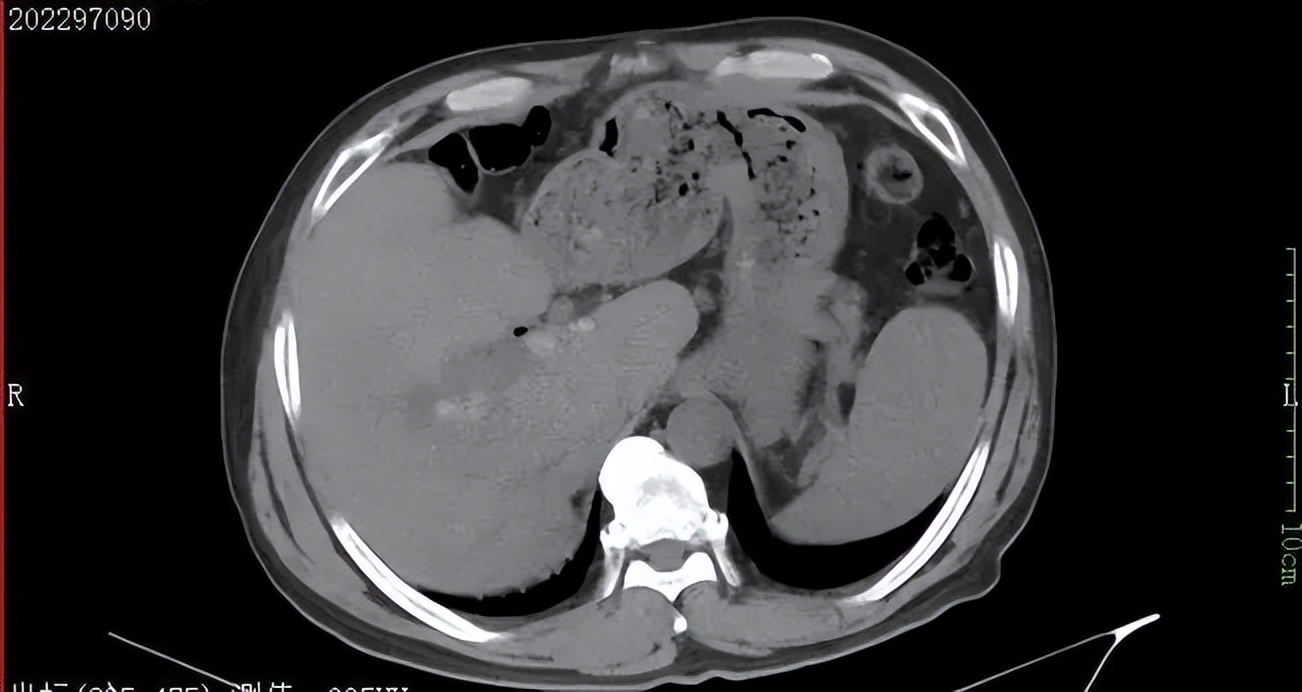

▲术前CT检查